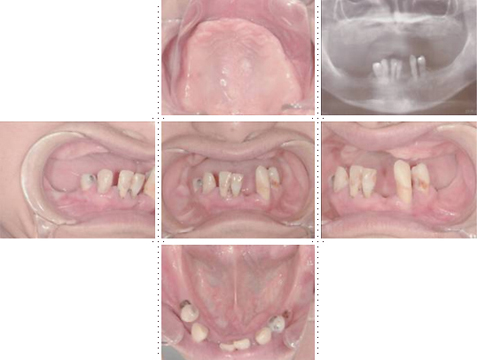

症例9

62才 男性

当院にてインプラント治療をされた患者さんからの紹介です。 一見すると残っている歯は多そうですが、実際はかなり歯周病が進行しており上下で15本の歯を抜かなければならない状態でした。 歯科治療における不安の1つとして、治療中に歯が無くては困るという相談をよく受けます。確かに噛めないのは不自由ですし、前歯であれば仕事など日常生活に大きな支障となります。しかし当院では抜歯した当日に義歯を装着できるシステムをとっており噛めない、見た目が気になるといった心配は全くありません。

このケースは局部床義歯の維持の為、犬歯を残し、抜歯後にすぐに入れられる義歯を使いながら、骨のあるところから適宜インプラントを埋入することで治療期間も負担も少なくてすみます。 インプラントは上顎8本、下顎8本を埋入しました。左下の奥は骨のしっかりしたところに傾斜埋入しました。 このような全顎ブリッジケースの咬み合わせは非常に難しいのですが、TEK(仮歯)を使った咬合採得方法にしてからはほぼ無調整でセットできるようになりました。 この咬合採得テクニックはインプラントセミナーで紹介し好評でした。